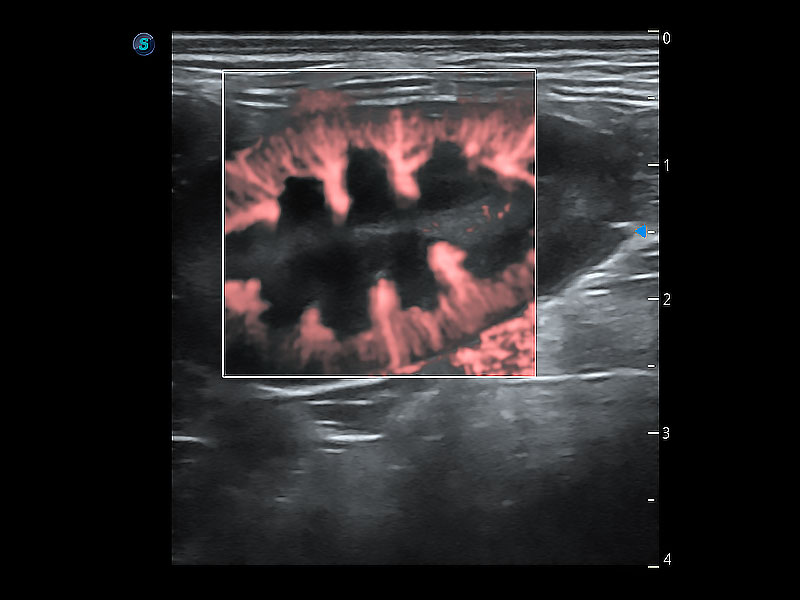

实时用颜色表示心肌组织运动,观察和定量组织的运动情況,对快速检测与评估心肌的灌注和活性、电传导及心肌收缩和舒张功能等均能提供重要的诊断信息。

通过心肌识别技术与二维斑点追踪技术相结合,对心脏的超声图像进行量化分析。计算心肌17个节段的应变、应变率、速度、位移等,并通过牛眼图的形式进行呈现。